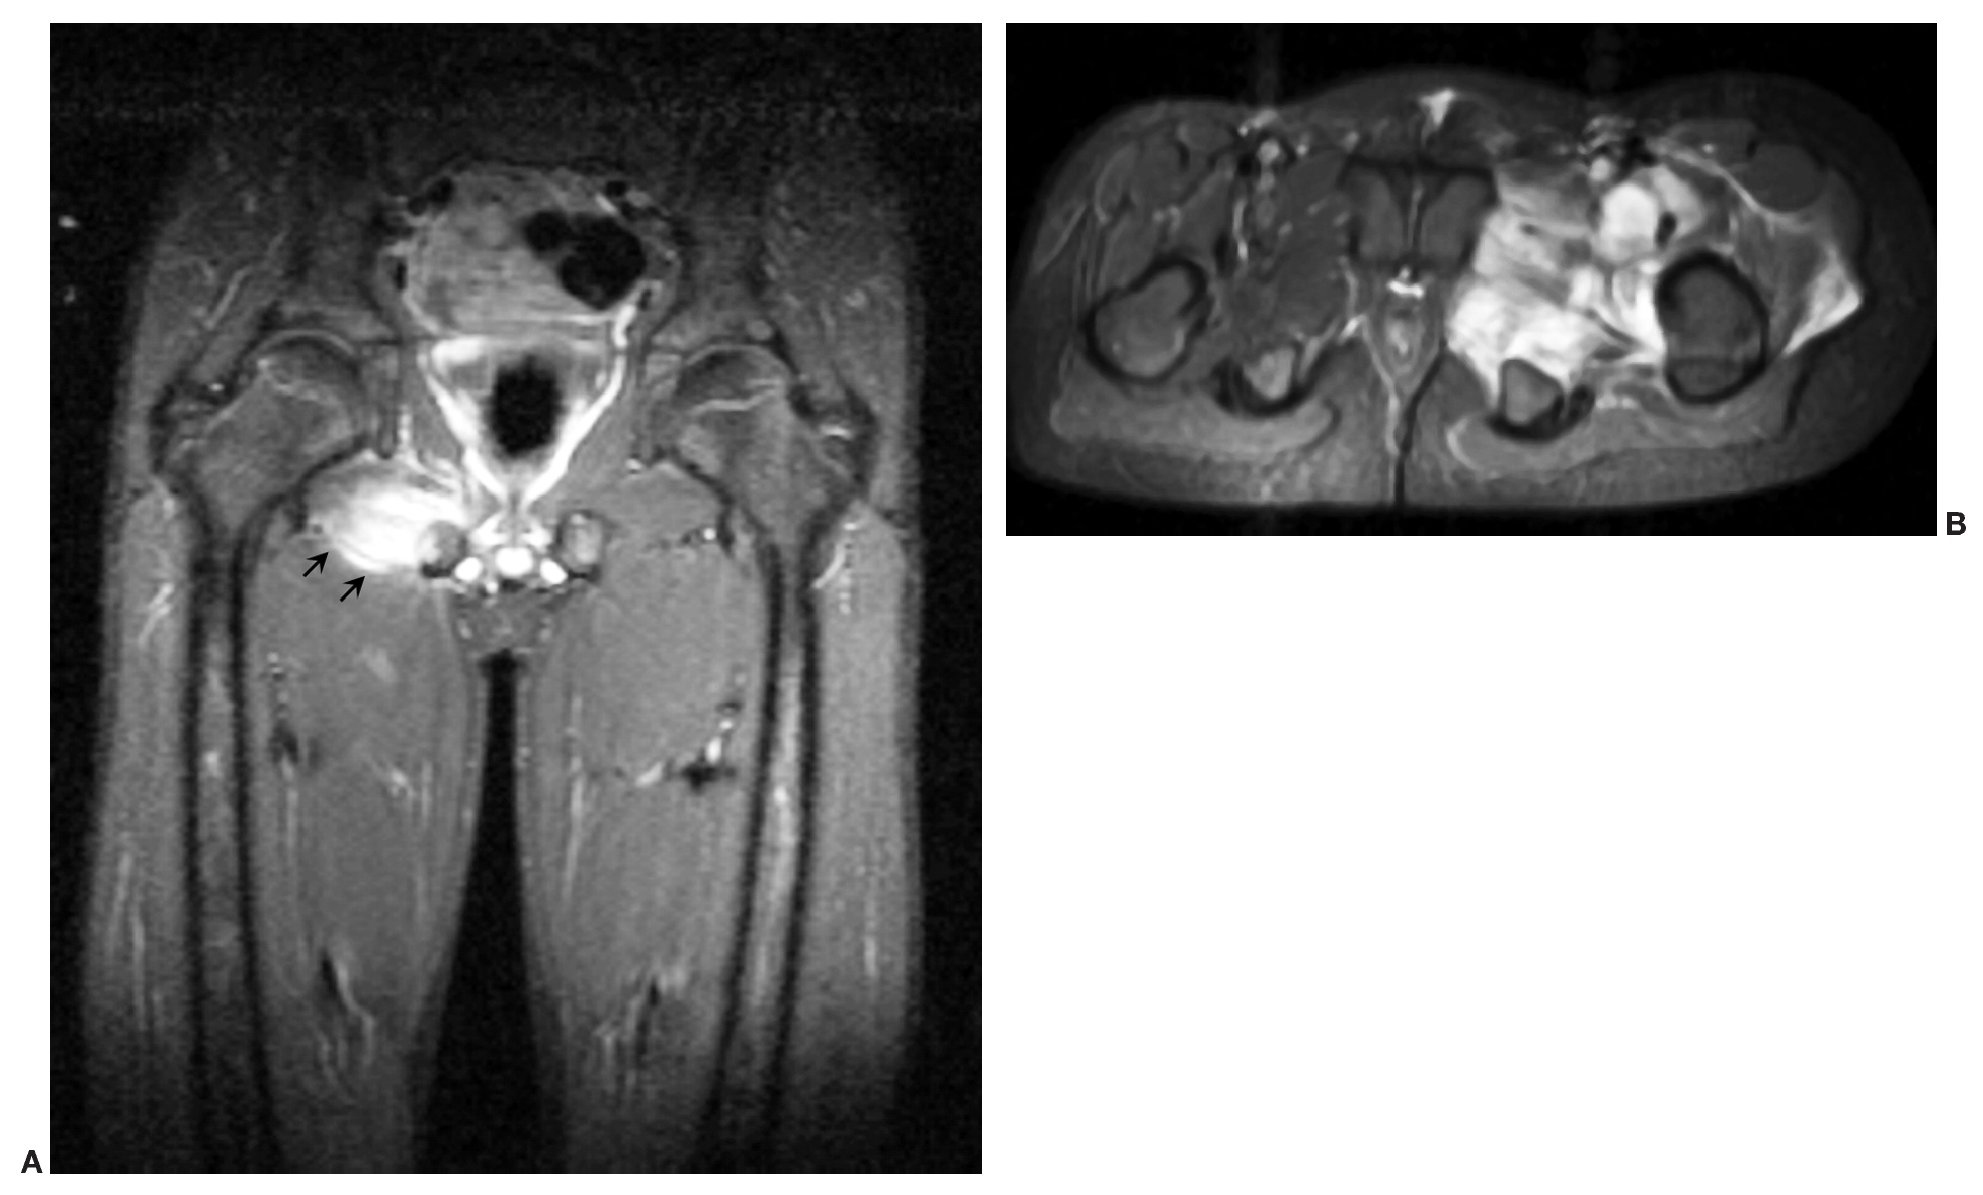

La piomiositis puede afectar a un músculo (fig. 2A) o a un grupo muscular2,4,12,15. Los músculos más comúnmente afectados son los del muslo y la región de la cadera: glúteos, aductores, obturador y psoas ilíaco (fig. 2B). La afectación preferente a este nivel hace que muchas veces el diagnóstico diferencial de la piomiositis sea extenso y se realice con artritis séptica, sinovitis transitoria, osteomielitis y/o procesos intraabdominales (apendicitis)16,17. En nuestra serie se evidencia esta predominancia, encontrando sólo tres casos de localización atípica, que afectaban a los músculos dorsal ancho, musculatura paravertebral cervical y lumbar (fig. 3).

Fig. 2. (A) Afectación de un único músculo. Resonancia magnética (RM) en secuencia coronal STIR mostrando una área de elevada señal que afecta al músculo obturador externo derecho. (B) RM en secuencia axial STIR mostrando la afectación de los diferentes grupos musculares de la pelvis, obturador interno, externo, pectíneo, psoas y glúteo menor.